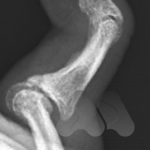

Carpal tunnel syndrome affects the median nerve that travels through a space that connects the forearm and hand at the front of the wrist. Pressure on the nerve, from many possible causes, can lead to a slowing of the electrical signals that supply sensation to the thumb, index and middle finger. It can lead to tingling and numbness in these fingers or the whole hand and can often be worse at night time.